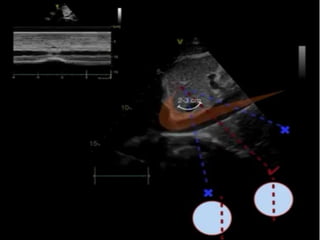

Technique

• We use low frequency probe or abdominal

probe.

• The transducer position is just below the

xiphisternum 1-2 cms to the right of midline

with the marker dot pointing towards the

sternum notch.

• M-mode line is placed through the IVC

2-3cms from the junction between IVC and

right atrium or 0.5-1 cm from the junction

of hepatic vien.

Technique • We uselow frequency probe or abdominal probe. • The transducer position is just below the xiphisternum 1-2 cms to the right of midline with the marker dot pointing towards the sternum notch.

• M-mode lineis placed through the IVC 2-3cms from the junction between IVC and right atrium or 0.5-1 cm from the junction of hepatic vien.